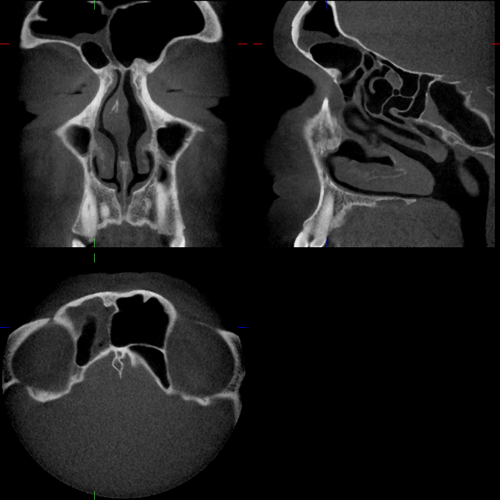

Bilder NNH

Kuhn'sche Zelle Mukozele SH Knochenneubildung Stirnhöhle sagittal Concha bullosa radikuläre Zyste